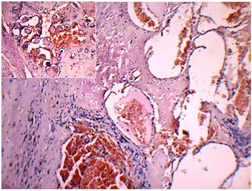

A left hemi-thyroidectomy was performed, and specimen was sent for histopathological evaluation. The specimen which was received was grey brown, globular, soft tissue mass and measured 6 x 5 x 3 cm. Cut-section revealed a well-encapsulated circumscribed lesion which measured 4.5 x 4 cm, and consisted of dark brown haemorrhagic areas, with irregular areas of fibrosis, myxoid change, foci of calcification and bone formation [Table/Fig-1]. The surrounding thyroid appeared normal. Microscopic examination revealed thyroid with a well encapsulated lesion, composed of large cavernous vascular spaces, with areas of haemorrhage, fibrosis, hyalinization, calcifications and bone formation [Table/Fig-2]. The surrounding thyroid tissue appeared normal. The final histological diagnosis of cavernous haemangioma of thyroid was made.

Cavernous spaces with blood and areas of fibrosis. Inset: Thyroid follicles admixed with vascular spaces (H&E X100)